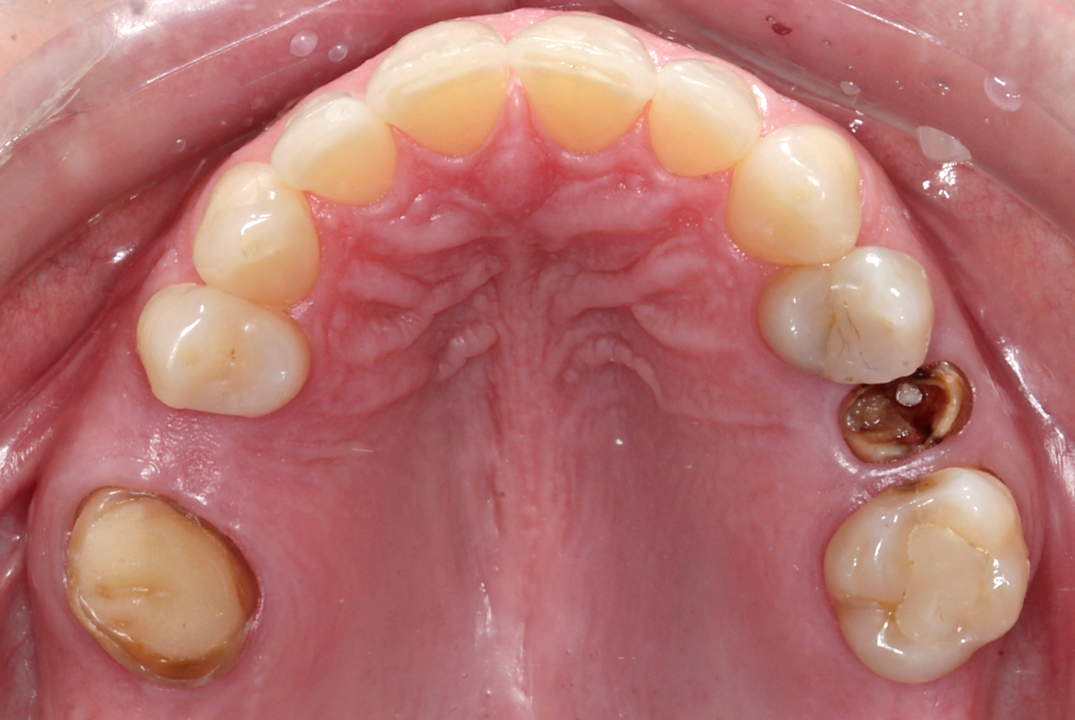

Initial situation

A 38-year-old female patient presented to the dental office reporting social discomfort when smiling, owing to the absence of both maxillary second premolars (Figs. 1a– c, Figs. 2a–c & 3). Clinical examination revealed that tooth #16 had an intra-radicular post and had been prepared for a crown, but the crown was missing, and a cavity was noted on the distal surface of tooth #14. Overall, the patient exhibited a healthy periodontal condition. She was a non-smoker and did not present with any comorbidities or systemic health issues. CBCT imaging showed adequate bone quality and quantity at both sites and no signs of acute infection. Additionally, a residual root was identified at site #15 beneath the already healed gingiva.

Fig. 3: Occlusal view of the initial situation.